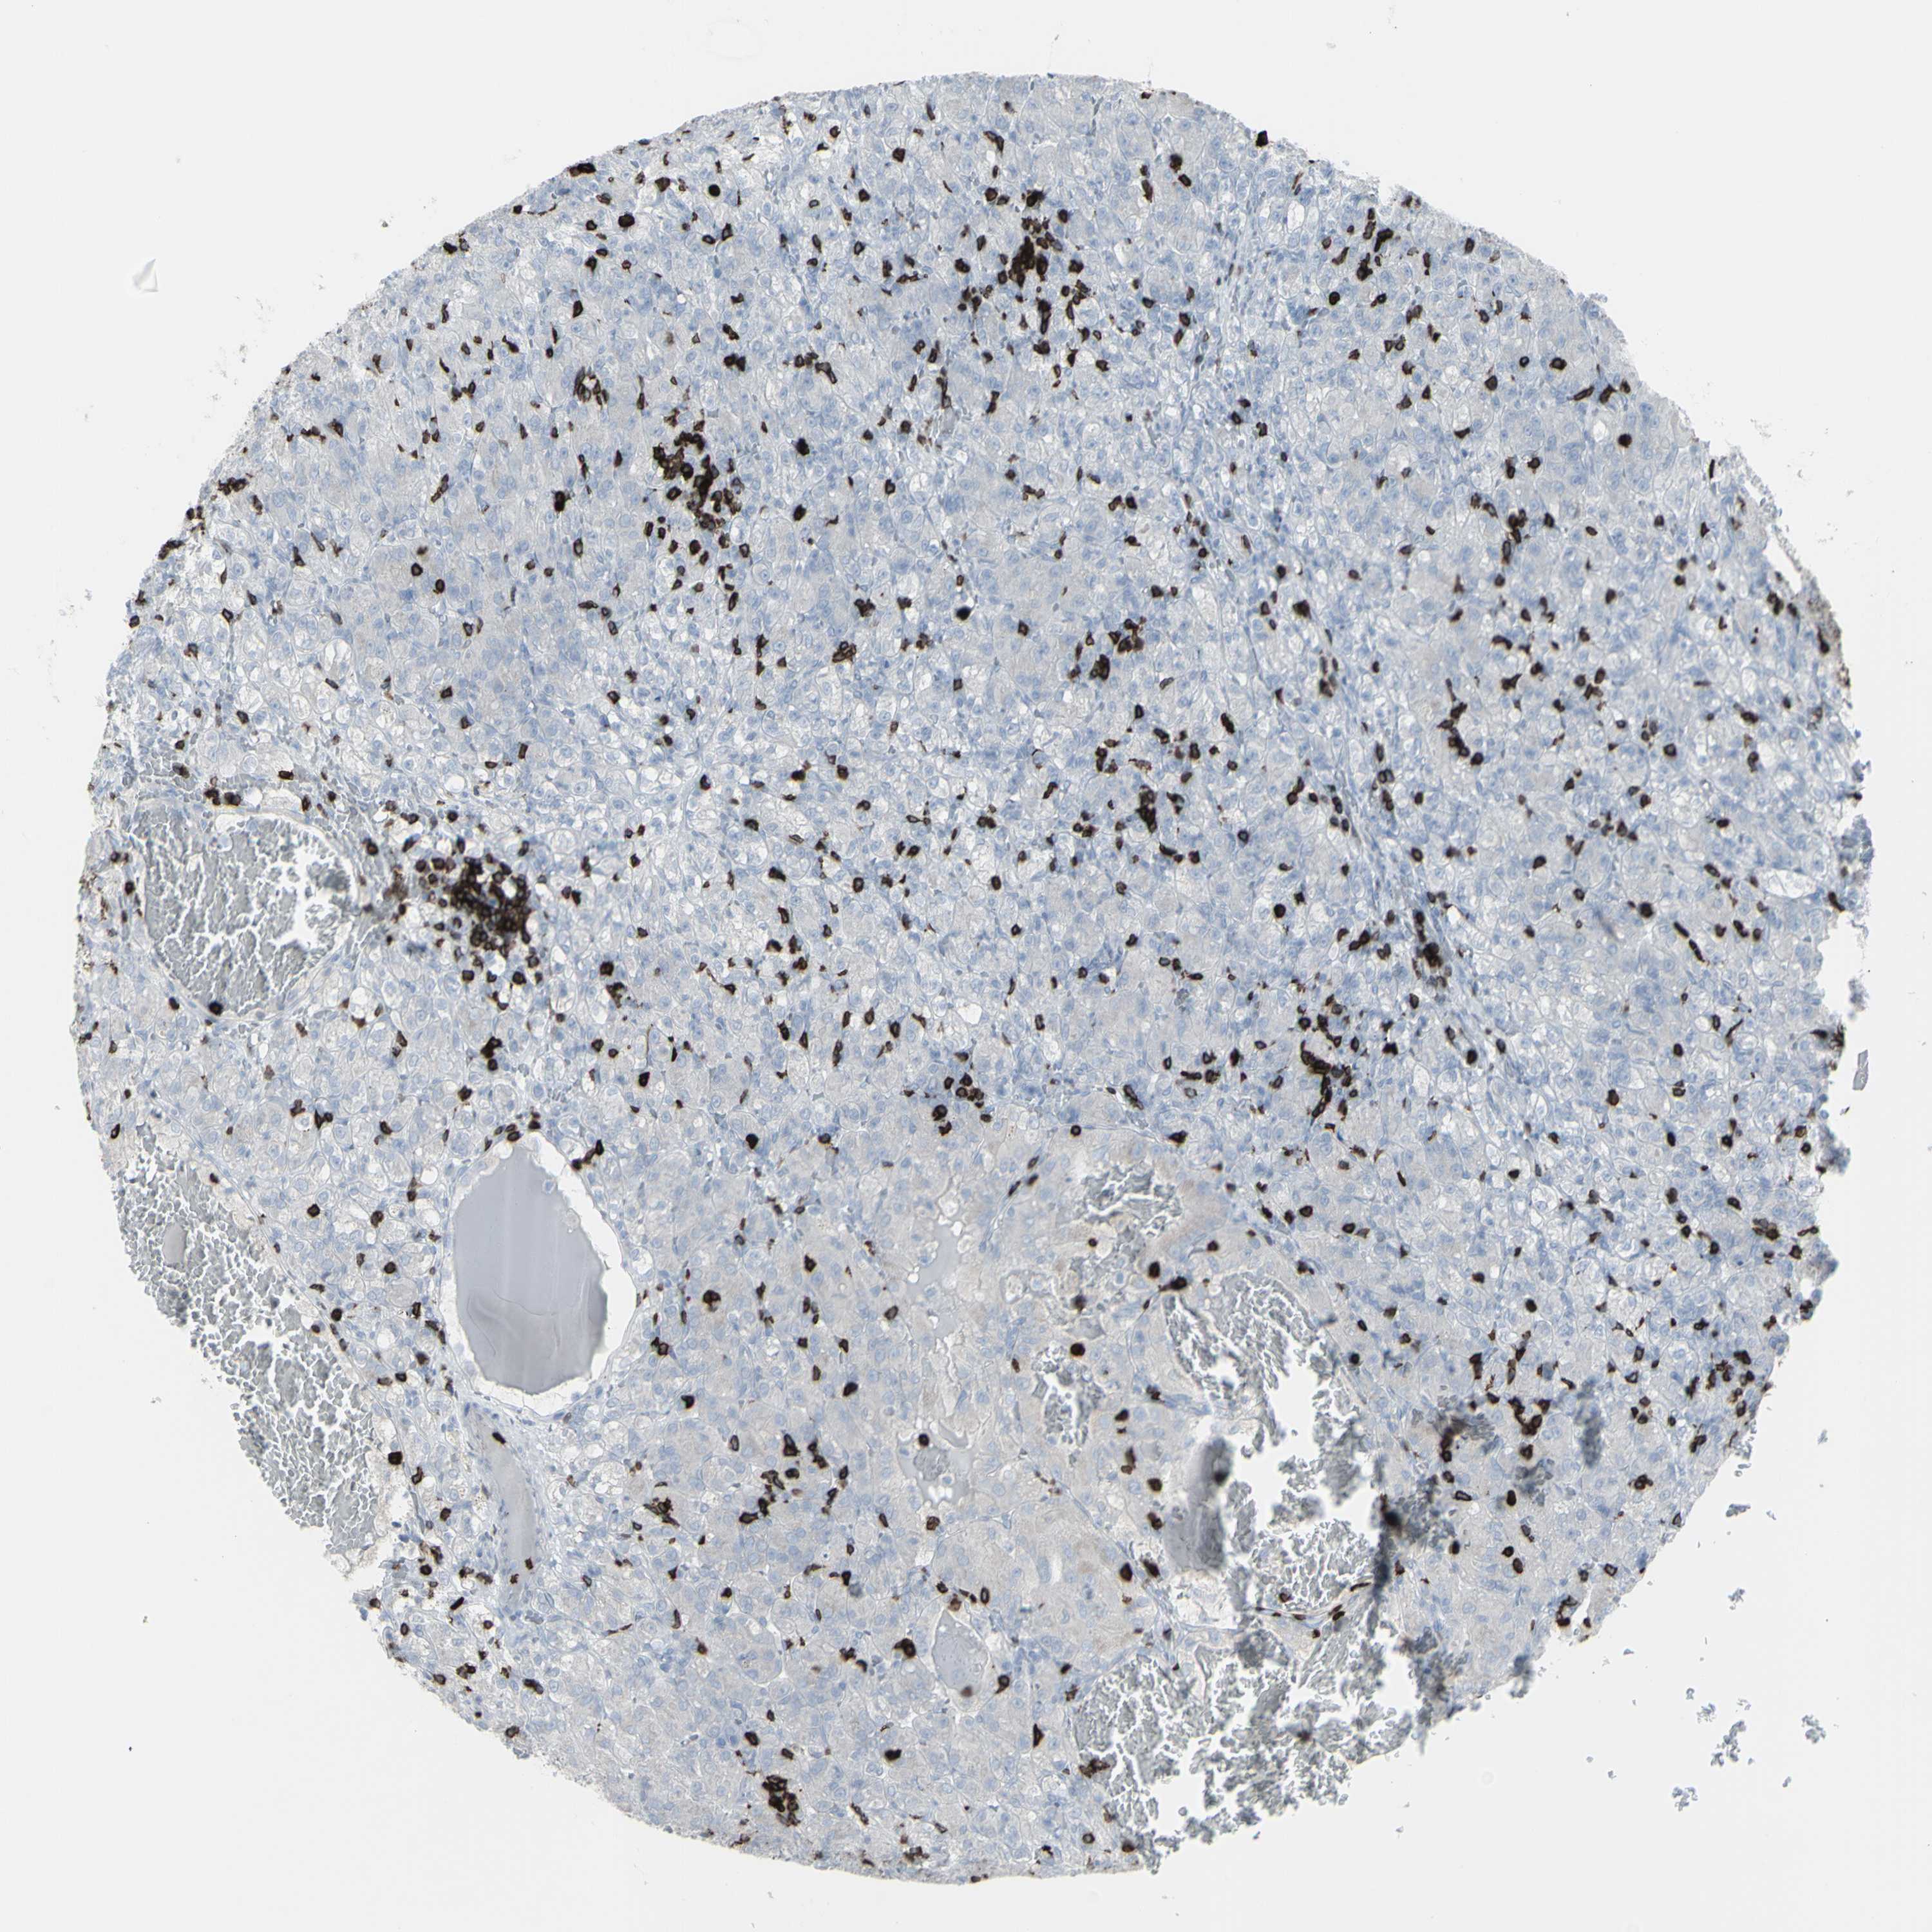

KIDNEY RENAL PAPILLARY CELL CARCINOMA (TCGA) - Interactive survival scatter ploti

The Survival Scatter plot shows the clinical status (i.e. dead or alive) for all individuals in the patient cohort, based on the same data that underlies the corresponding Kaplan-Meier plots. Patients that are alive at last time for follow-up are shown in blue and patients who have died during the study are shown in red.

The x-axis shows the expression levels (FPKM) of the investigated gene in the tumor tissue at the time of diagnosis. The y-axis shows the follow-up time after diagnosis (years). Both axes are complimented with kernel density curves demonstrating the data density over the axes. The top density plot shows the expression levels (FPKM) distribution among dead (red) and alive patients (blue). The right density plot shows the data density of the survived years of dead patients with high and low expression levels respectively, stratified using the cutoff indicated by the vertical dashed line through the Survival Scatter plot. This cutoff is automatically defined based on the FPKM cutoff that minimizes the p-score. The cutoff can be changed by dragging the vertical line or by entering a cutoff value in the square labeled "Current cut-off".

Under the Survival Scatter plot the p-score landscape (black curve; left axis) is shown together with dead median separation (red curve; right axis). Dead median separation is the difference in median mRNA expression between patients who have died with high and low expression, respectively. It is calculated as follows: median FPKM expression of dead patients with high expression - median FPKM expression of dead patients with low expression. This is intended to aid the user in visually exploring custom cutoffs and the associated p-scores and dead median separation.

Individual patient data is displayed and can be filtered by clicking on one or more of the category buttons on the top of the page. Categories describing expression level and patient information include: high, low, alive, dead, female, male and tumor stages. The scale of the x-axis can be toggled between linear and log-scale by clicking on the "x log" button. Mouse-over function shows TCGA ID, patient information and mRNA expression (FPKM) for each patient.

& Survival analysisi

Kaplan-Meier plots summarize results from analysis of correlation between mRNA expression level and patient survival. Patients were divided based on level of expression into one of the two groups "low" (under cut off) or "high" (over cut off). X-axis shows time for survival (years) and y-axis shows the probability of survival, where 1.0 corresponds to 100 percent.

CD247 is not prognostic in Kidney Renal Papillary Cell Carcinoma (TCGA)

Best expression cut offi

Based on the FPKM value of each gene, patients were classified into two groups and association between prognosis (survival) and gene expression (FPKM) was examined. The best expression cut-off refers the FPKM value that yields maximal difference with regard to survival between the two groups at the lowest log-rank P-value. Best expression cut-off was selected based on survival analysis .

When clicking on this number, the vertical dashed line indicating cut-off, the interactive survival plot, and the Kaplan-Meier curve will be adjusted to show results based on the best expression cut-off.

: 3.06